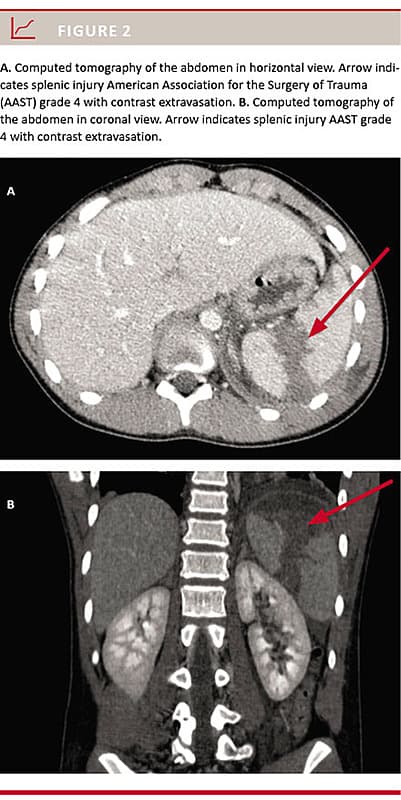

All 34 patients were scheduled for NOM. Two (5.9%) patients later needed surgical intervention. One patient (AAST grade 5 on initial CT evaluation and grade 4 on CT re-evaluation) had a splenectomy performed due to impaired circulation within the first 24 hours, and the other had a laparotomy with suturing of the small intestines due to perforation (AAST grade 1 on initial CT evaluation and grade 2 on CT re-evaluation). During the course of NOM, two (5.9%) patients underwent SAE, one due to diffuse bleeding and one due to a pseudo-aneurism (Figure 2 and Figure 3, respectively). Subsequently, all patients were considered circulatorily stable. Thus, the NOM success rate was 88% (95% CI: 73-97%) without SAE and 94% (95% CI: 80-99%) with SAE.